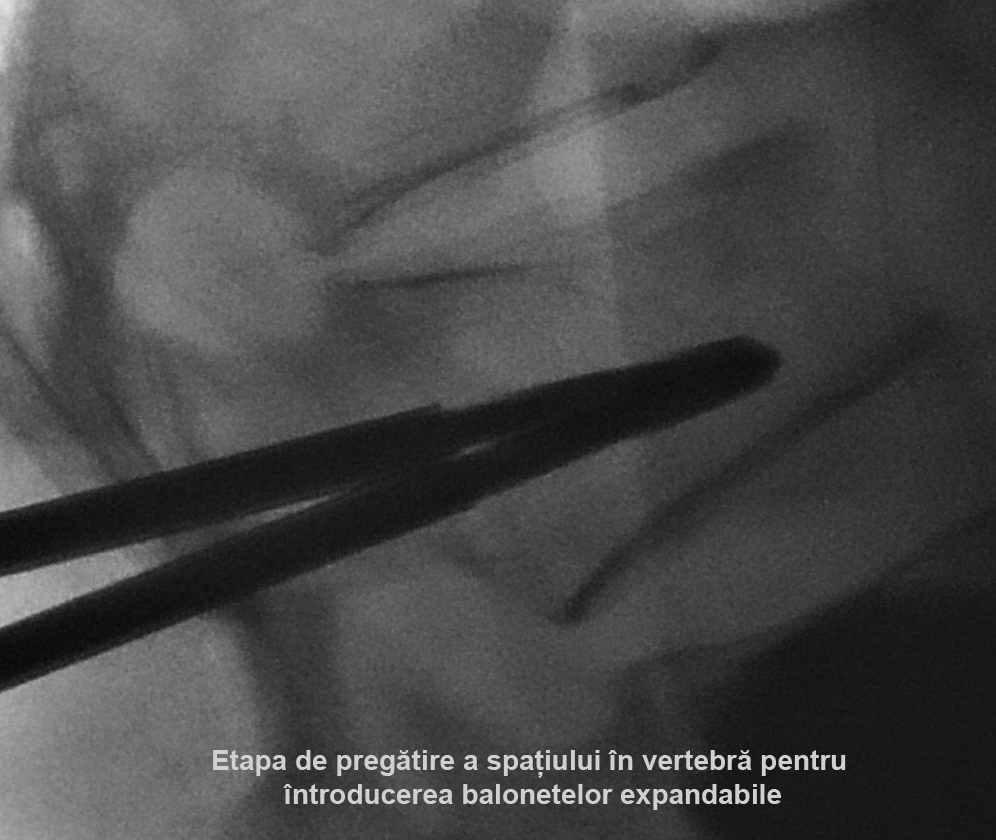

Kyfoplastia reprezintă o procedură minim invazivă în timpul căreia chirurgul introduce în corpul vertebral un tub cu un balon expandabil. Sub control fluoroscopic are loc expansionarea balonului în corpul vertebral, cu restabilirea înălţimii corpului vertebral şi corijarea diformităţii kifotice. Ulterior, în cavitatea formată de balon, se introduce cimentul acrilic, ceea ce contribuie la consolidarea vertebrei.

Realizarea intervenţiilor percutanate de acest tip presupune utilizarea unui fluoroscop intraoperatoriu, cu scopul de a reduce la minim complicaţiile (cum ar fi, leziuni ale structurilor nervoase, scurgerea cimentului extracorporeal, embolii venoase, etc.). În cazul pacientei noastre, a fost utilizată instalaţia de Angiografie tridimensională (3D) Siemens ”Artis Zee”, disponibil în sala de operaţii Hybrid a Spitalului Clinic Republican, care asigură o calitate excepţională a imaginilor intraoperatorii.

Vertebroplastia percutană a corpului LII a fost executată prin abord unilateral transpedicular pe stânga, în timp ce Kyfoplastia cu baloane expandabile a corpului vertebral LI - prin abord bilateral transpedicular pe stânga.